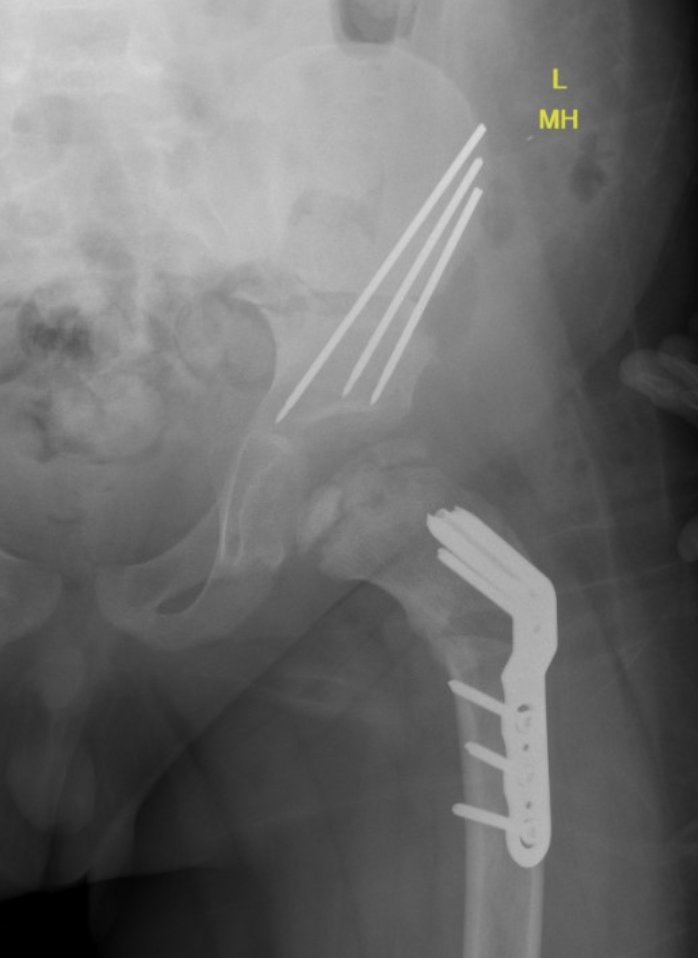

Salter pelvis osteotomy

Concept

Redirects acetabulum to provide coverage for anterolateral head

Smith Peterson approach

- iliac apophysis split

- release direct head of rectus and psoas tendon

- subperiosteal dissection to sciatic notch reflecting gluteals

Osteotomy

- through greater sciatic notch to between ASIS and AIIS

- Gigli saw passed around greater sciatic notch

- osteotomy posterior to anterior

- acetabulum rotated anteriorly and laterally

- 15 mm triangular graft from iliac crest apophysis

- secure with K wire fixation

Repair split in iliac apophysis

Combined Femoral and Pelvic Osteotomy